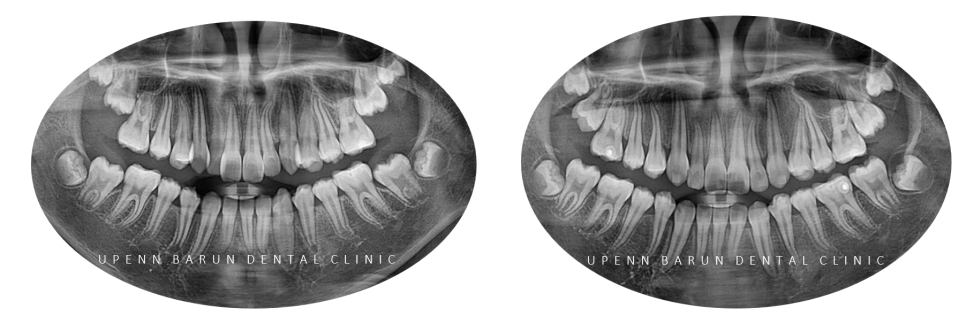

교정기간: 23/8 ~ 24/11

1st Clincheck(25개 장치)

교정기간: 23/8~ 24/1

25개의 장치를 통해 첫번째 클린체크를 마친후의 사진입니다

첫번째 클린체크만으로도 완성도 있게 교정이 잘 되었습니다 :)

2nd Clincheck(26개 장치)

교정기간: 24/2~ 24/7

첫번째 클린체크에서는 치아 배열에 중점을 두었다면

완벽함을 추구하는 김승우 원장님께서는

두번째엔 좀더 세심한 디자인을 통해

위 아랫니의 교합을 보완해주었습니다.

청소년인비절라인 두번째 클린체크 에서는

첫번째 클린체크에서 어태치먼트가 추가되어

이전의 클린체크를 보완해 교정치료의 완성도를 높여 줍니다.

3rd Clincheck(12개 장치)

교정기간: 24/7~24/11

마지막 클린체크인 12개의 장치를 통해 교정이 마무리된 사진입니다.

김원장님의 세심한 진료와 환자분의 높은 협조도로

발치 하지 않고 반대교합을 개선하고

치열을 가지런하게 마무리 해드렸습니다.